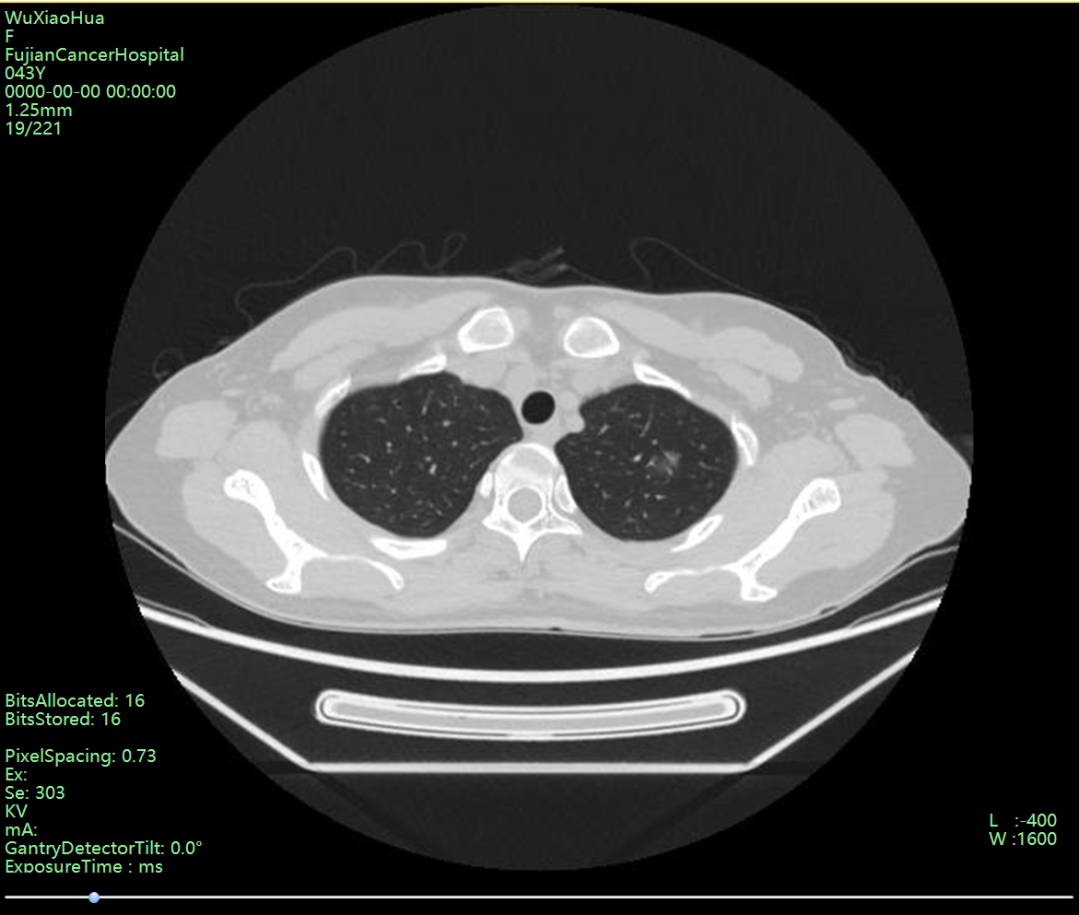

近日,福建省肿瘤医院胸部肿瘤外科朱坤寿主任医师团队使用LungCare电磁导航系统对一例左肺上叶尖亚段混杂磨玻璃结节进行超细纤维支气管镜下的染色精准定位,并行胸腔镜下行左肺上叶尖亚段楔形切除,手术过程顺利,术中冰冻病理为微小浸润性腺癌。 患者,吴女士,43岁,查胸部CT提示:左肺上叶尖亚段可见一混杂磨玻璃结节影,边缘模糊,大小约为1.3X1.2cm,内见小血管穿行,由于结节较小、位置较外周,常规定位手段定位难度较大,朱坤寿主任医师及林绍峰副主任医师术前充分讨论,决定在LungCare电磁导航系统引导下创新性地使用超细纤维支气管镜进行定位染色。 朱坤寿主任表示,传统电磁导航引导下的气管镜手术受限于气管镜外径较粗,一般只能先使用单腔管,之后再替换为双腔管行肺切除术,增加了麻醉的步骤与时间。而本次手术,在诱导麻醉后常规双腔气管插管,手术团队采用外径3.0mm、工作通道1.2mm的超细纤维支气管镜,由电磁导航实时引导快速抵达既定位置,随后继续推送由定位导线引导的超细延长鞘管至病灶附近胸膜处,于此处打入0.2ml美兰染色液,随后缓慢推入空气让染色液逐渐渗透至病灶附近胸膜区域,实现快速精准定位。 规划重建后的肺部病灶及路径 导航路径